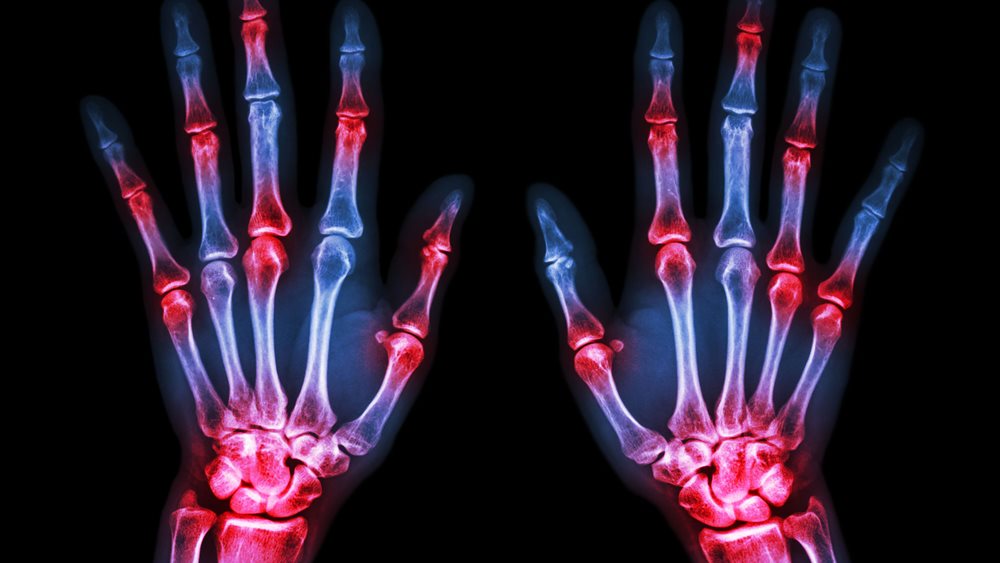

Σημαντική έγκριση νέας θεραπείας για τους ασθενείς με ρευματοειδή αρθρίτιδα

Η έγκριση του upadacitinib από την Ευρωπαϊκή Επιτροπή για ασθενείς με μέτρια έως σοβαρή ρευματοειδή αρθρίτιδα είναι ένα από τα τελευταία "καλά νέα" της χρονιάς για ασθενείς με τη συγκεκριμένη νόσο. "Σχεδόν 3 εκατομμύρια άνθρωποι στην Ευρώπη ζουν με ρευματοειδή αρθρίτιδα, η πλειονότητα των οποίων δεν επιτυγχάνει ύφεση και ενδέχεται να υποφέρει από πόνο, κόπωση, πρωινή δυσκαμψία στις αρθρώσεις και εξάρσεις", δήλωσε ο Καθηγητής Ronald van Vollenhoven, M.D., Ph.D., Κέντρο Ρευματολογίας και Ανοσολογίας του Άμστερνταμ στις Κάτω Χώρες. "Όπως διαπιστώνεται στο μεγάλο αυτό πρόγραμμα κλινικών μελετών Φάσης 3 στη ρευματοειδή αρθρίτιδα, το upadacitinib έχει τη δυνατότητα να βελτιώσει σημαντικά τα σημεία και τα συμπτώματα της νόσου και να βοηθήσει περισσότερους ασθενείς να πετύχουν ύφεση ή χαμηλή ενεργότητα της νόσου".